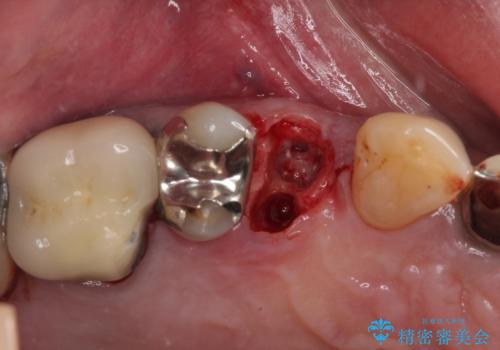

当院での根管治療および歯周外科治療を併用した保存療法、並びに1DAYインプラントによる短期間インプラント治療の双方をご説明し、即日でインプラント治療を選択されました。

仮歯を用意した上で、抜歯即時埋入・即時荷重インプラントによる補綴治療を行うこととしました。

従来のインプラント治療について回った3回の外科手術や半年移動の治療期間とは無縁の、短期間治療を達成することができました。